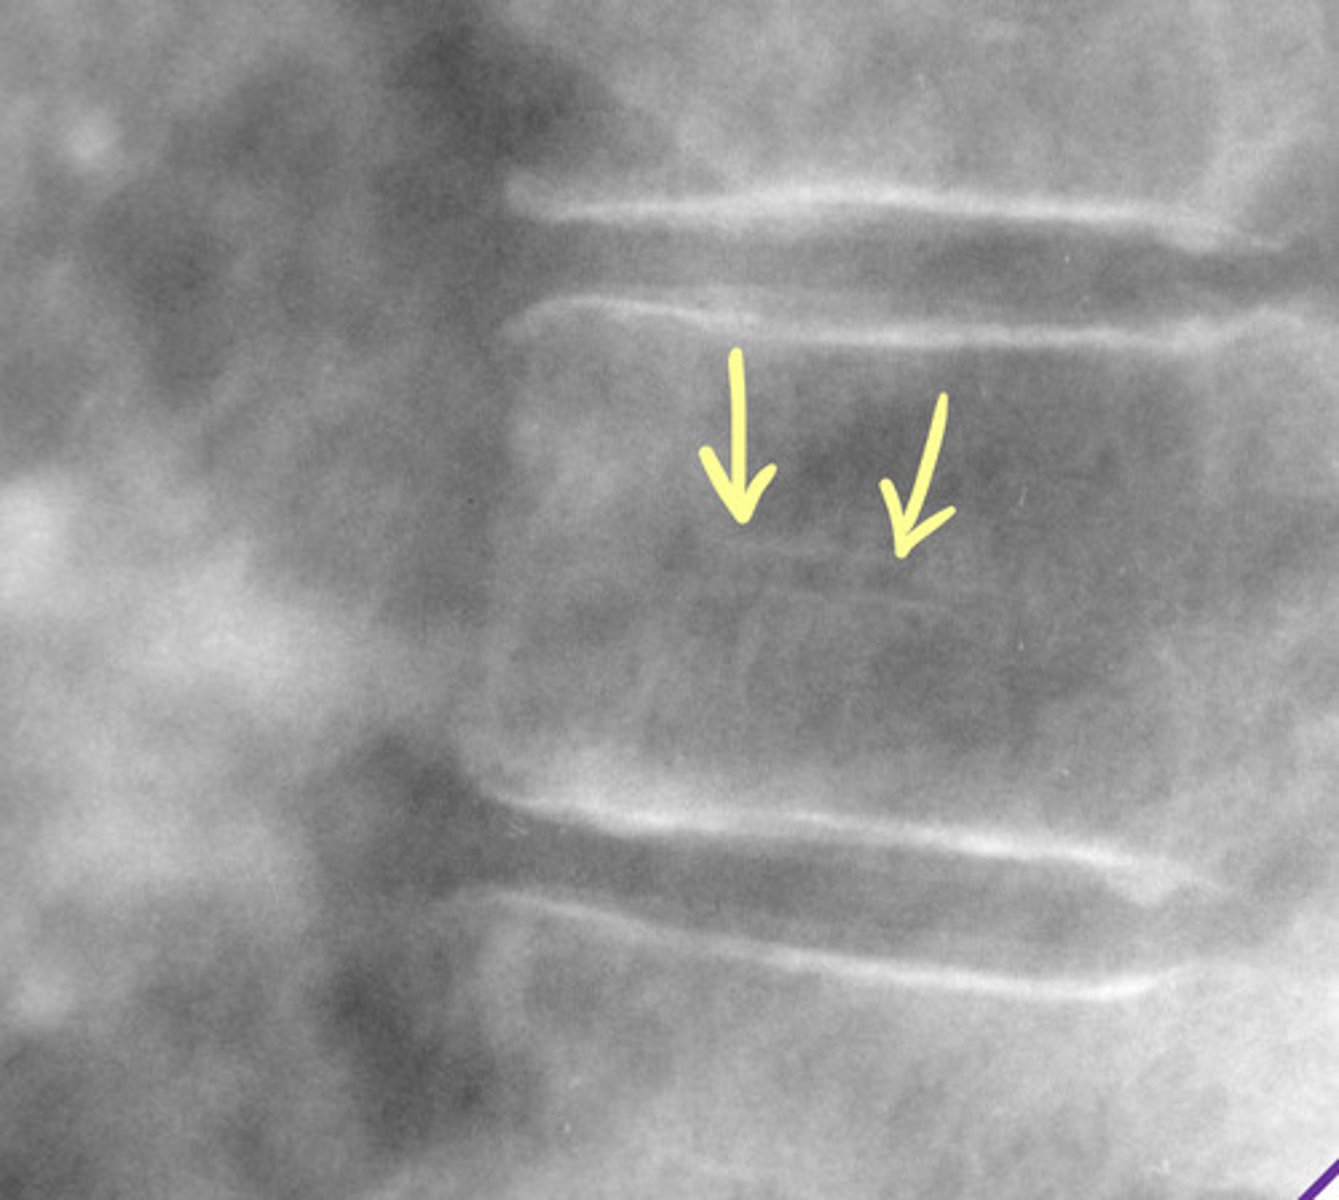

Hahn Vascular Cleft/Groove/Canal

Embryonic vascular channel = vertebral vascular foramina (Hahn Canal)

Do not mistake for a fracture

NO clinical significance

What does the Hahn Canal transmit?

— basivertebral veins

— intraosseous nutrient arteries

— basivertebral nerve